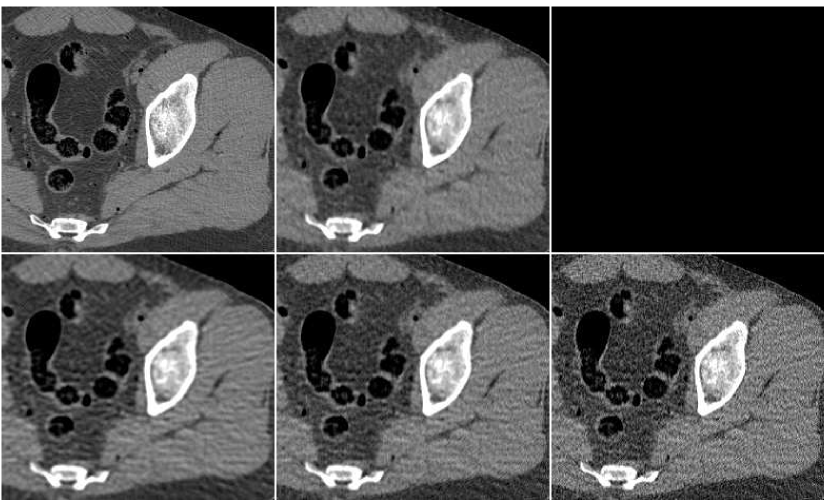

In Figure 10 we display the fusion result along with individual PWLS reconstructions, used in the fusion process. The lower part of the figure contains the absolute-valued error images. The fusion result has a higher visual quality than any of the three underlying images. Comparing to those images, the noise level in the fusion image is the lowest, and the tissue texture is closer to the original. The sharpness is the same as in the lower middle PWLS image. The SNR values (stated in the Figure) also point to the improvement in quality. The SSIM of the fusion image is , while the sequence of PWLS results have the SSIM values of (corresponding to the lower row of Figure 10, left to right). A reconstruction of an additional test image is displayed in Figure 11. The effect of the fusion observed here is similar to the one in the previous reconstruction. We conclude that the ANN-based fusion can contribute also to the iterative reconstruction, without requiring any additional iterations; the computational cost of the fusion, exercised after the reconstruction, is lower by an order of magnitude than that of the iterative process.

In order to test the robustness of the training results, we apply the ANN trained with the thigh sections, for a reconstruction of images of other body parts – sections of the head and the abdomen. Reconstruction results are presented in Figure 13 in the same order as in the previous comparison: middle image in the upper row is the result of fusion, which components are presented in the lower row. The head reconstruction is improved substantially by the fusion process, as visual observation shows. However, the SNR values (given in Table II) point to the favor of the PWLS image corresponding to iterations (lower middle image). The highest SSIM value does belong to the fusion result, though. In the case of the abdomen section, the fusion image is similar to the -iterations version but contains less noise; its quantitative measures are somewhat better than those of the individual PWLS images.